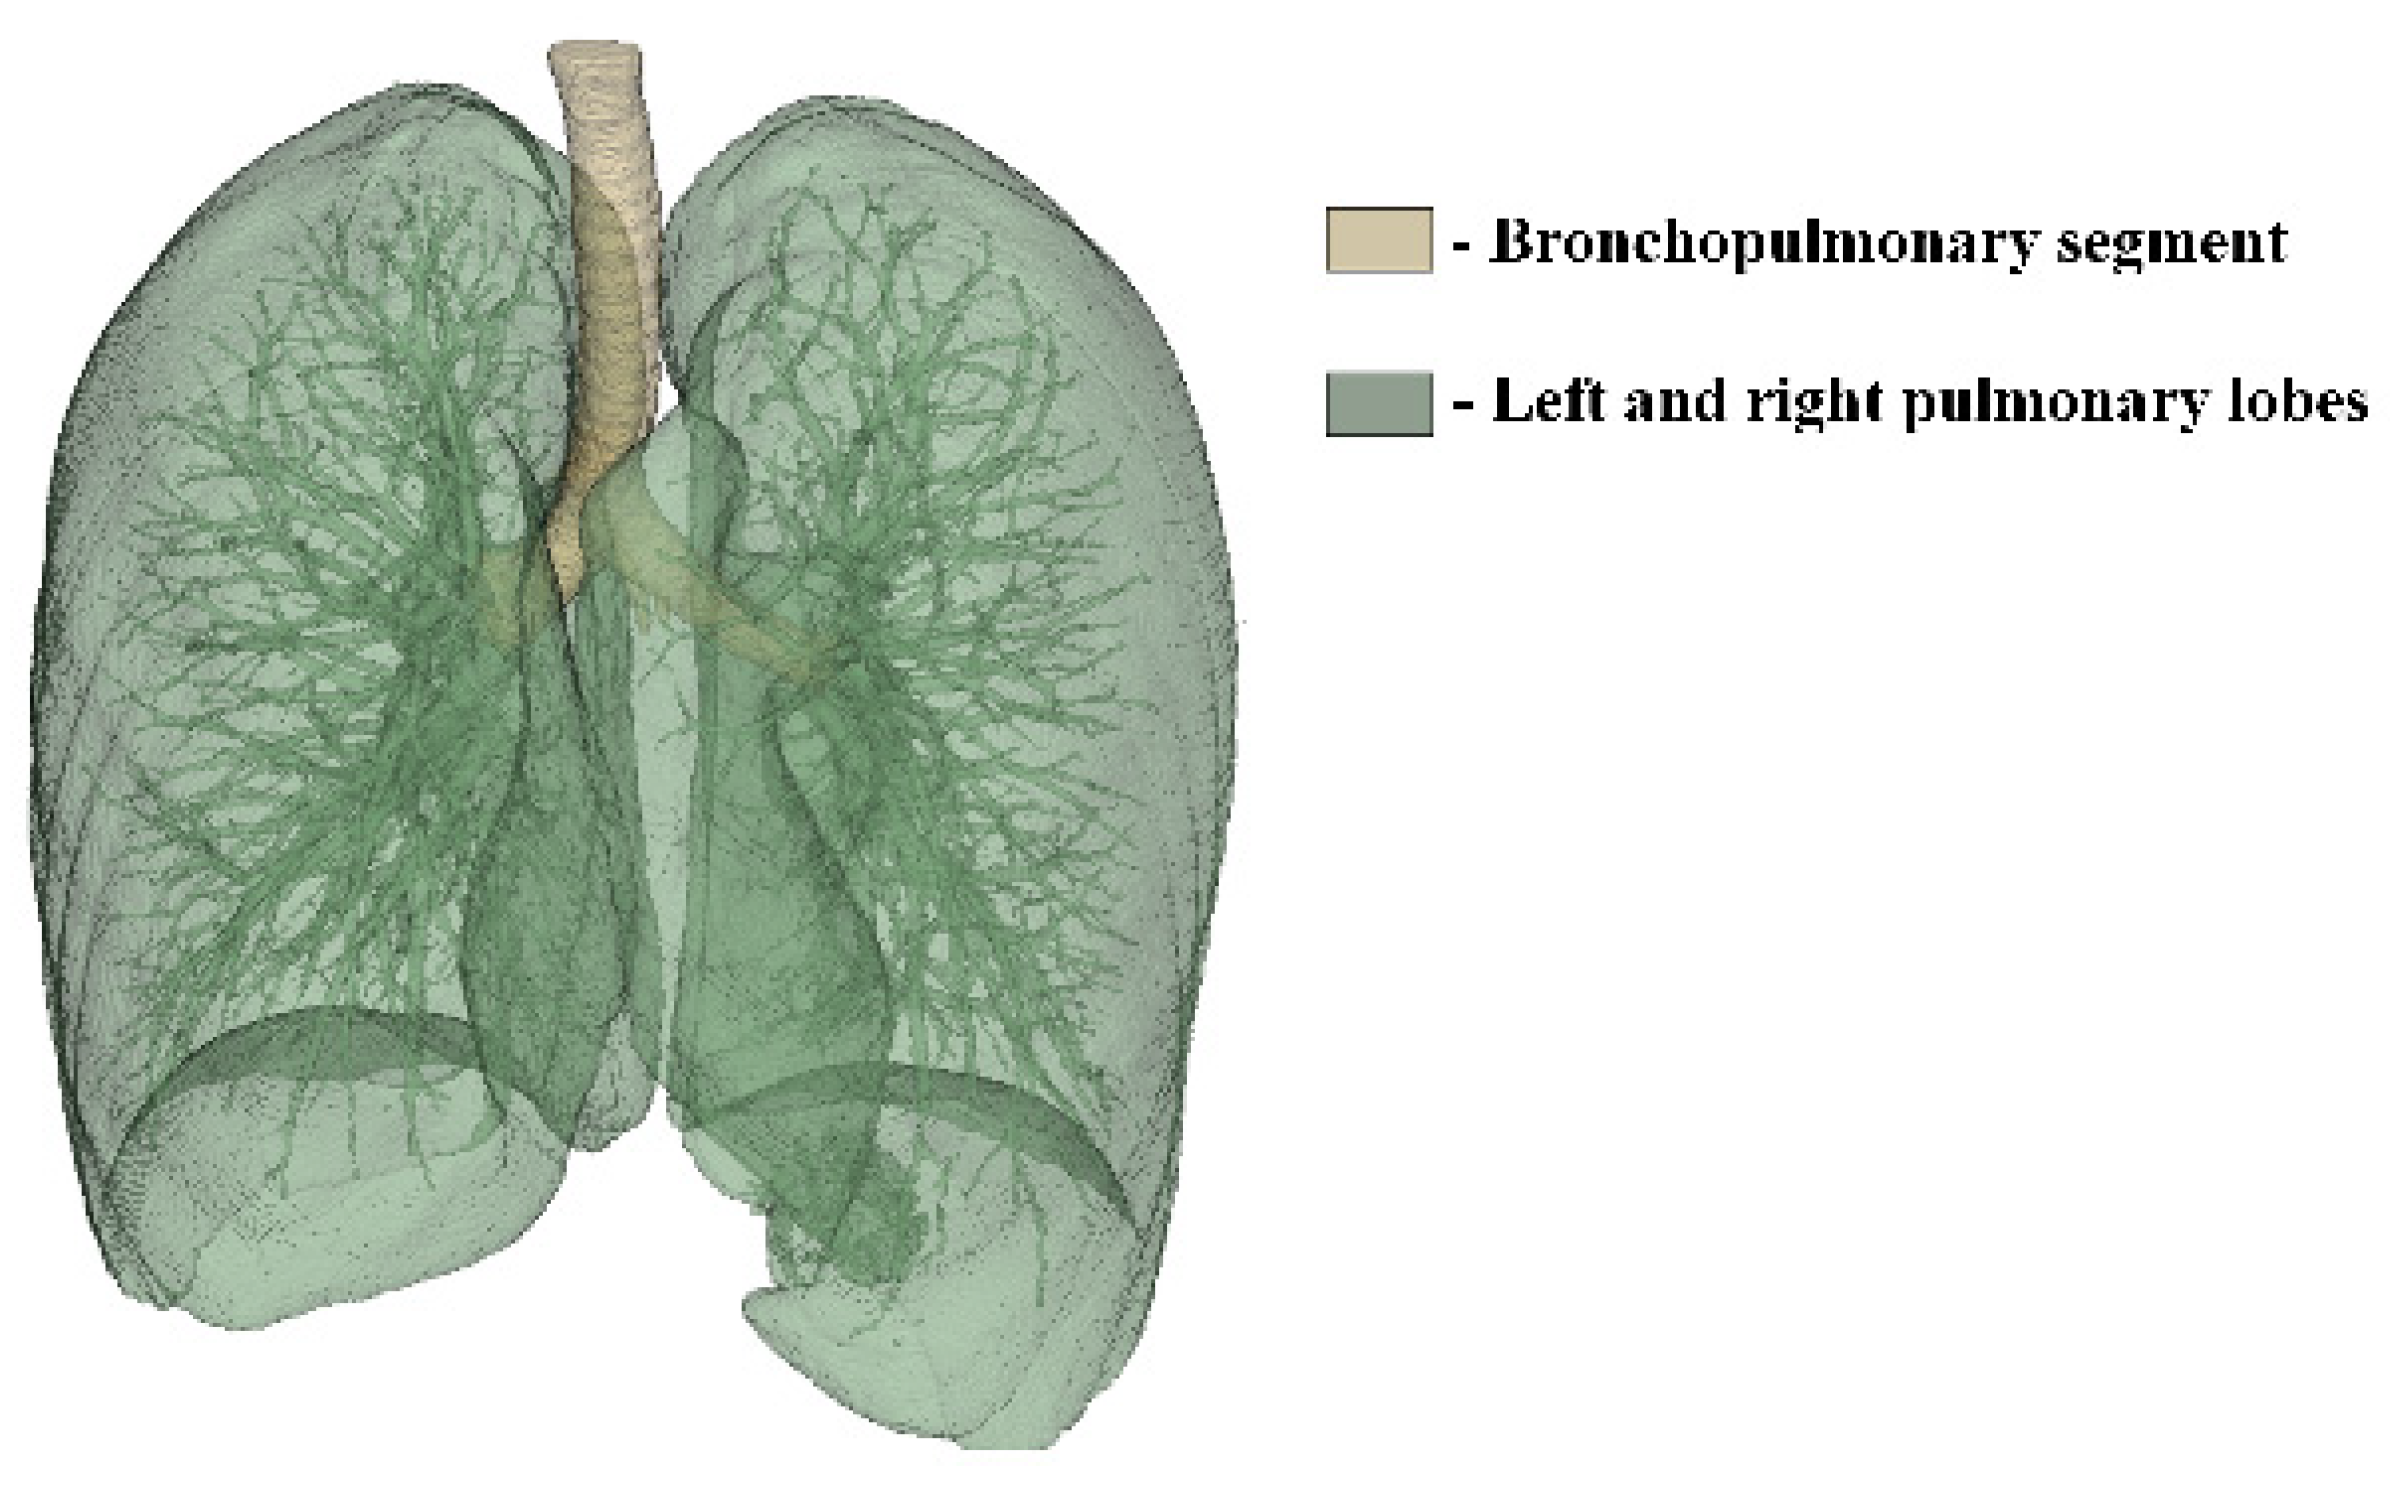

To generate a 3D model of the lower respiratory tract, CT images of the lungs were loaded into the 3D Slicer program and displayed in three projections. Figure 6 shows the result of the automatic generation of a 3D lung model.

The automatic generation of the lungs’ 3D model from CT images resulted in the amalgamation of the bronchopulmonary trunk and pulmonary lobes into a singular 3D model, lacking the capability to differentiate between them. However, for the subsequent modeling of drug dispersion within the lower respiratory tract, isolating the bronchopulmonary trunk becomes imperative. Hence, CT images, loaded in three projections, underwent layer-by-layer processing using the Segment Editor toolkit in the 3D Slicer program. This meticulous process of identifying the free volume of the airways enabled the generation of a distinct 3D model representing the bronchopulmonary trunk. The outcome of processing the CT lung images and the resulting 3D model are depicted in Figure 7.

Figure 6. Automatically generated 3D model of the lungs in the 3D Slicer program.

Computation 12 00134 g006

Figure 7. Layer−by−layer processing of CT images in three projections: frontal plane (a); sagittal plane (b); axial plane (c); generated 3D model of the bronchopulmonary trunk (d).